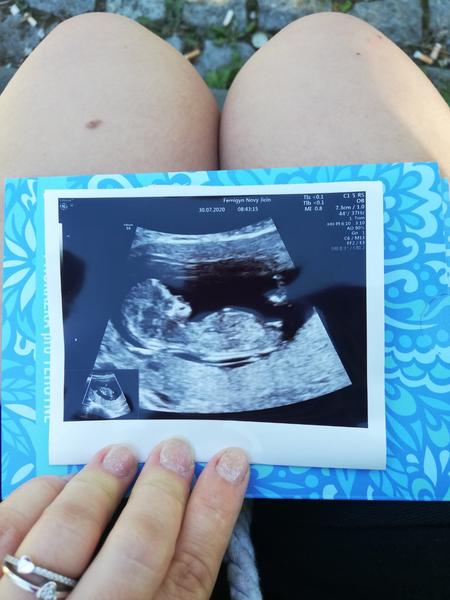

Já mám teď tady takové fotky z 12 týdne. Zítra jdu na screening tak jsem zvědavá jestli něco uvidí. Tipnete si někdo? 😃